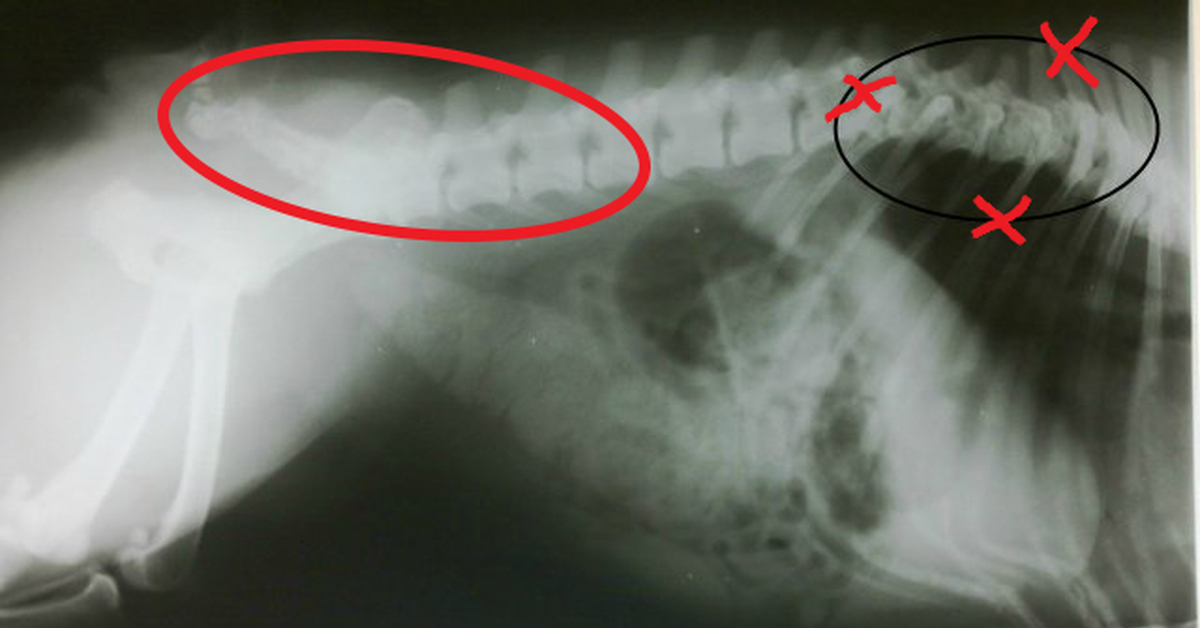

Рентгенологическая диагностика саркомы у кошек

Раздел: Визуальный дайджест